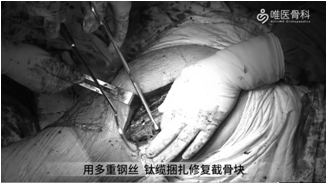

④给予多重钢丝、钛缆捆扎修复截骨块。取下试模,安装陶瓷股骨头,复位后再次检查髋关节稳定性和下肢长度。